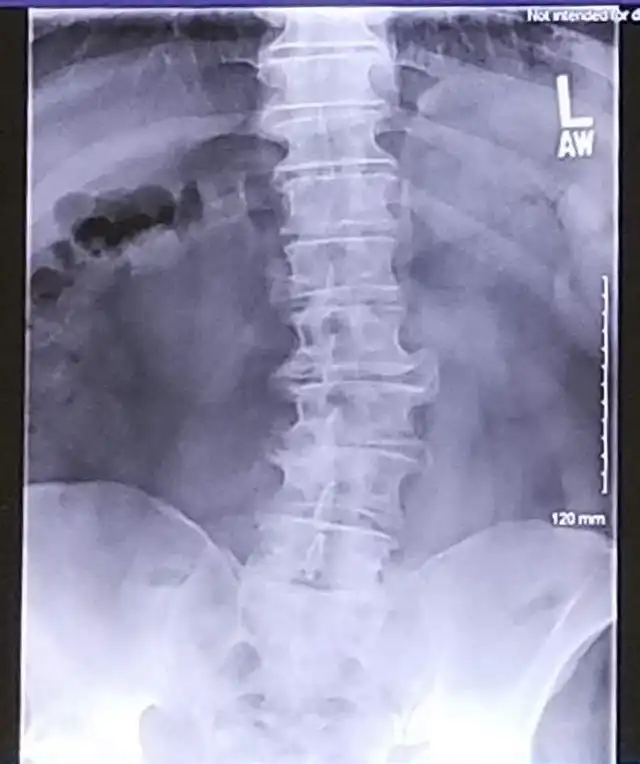

13. Отправил жене рентген своего позвоночника, в надежде получить немного сочувствия и поддержки. А она написала: "Твое тело как проселочная дорога, лол"